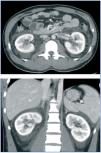

Los síntomas de la FHSR por lo general se desarrollan dentro de 1 a 2 semanas después de la exposición a material infeccioso, pero en casos raros, pueden tardar hasta 8 semanas en desarrollarse. Los síntomas iniciales comienzan repentinamente e incluyen dolores de cabeza intensos, dolor abdominal y de espalda, fiebre, escalofríos, náuseas y visión borrosa. Los individuos pueden tener enrojecimiento de la cara, inflamación o enrojecimiento de los ojos, o una erupción cutánea. Los síntomas posteriores pueden incluir presión arterial baja, shock agudo, pérdida vascular e insuficiencia renal aguda, lo que puede causar una sobrecarga de líquidos grave.

La gravedad de la enfermedad varía dependiendo del virus que causa la infección. Las infecciones por los virus Hantaan y Dobrava suelen causar síntomas graves, mientras que las infecciones de los virus Seúl, Saaremaa, y Puumala son por lo general más moderadas. La recuperación completa puede tardar semanas o meses.[2]